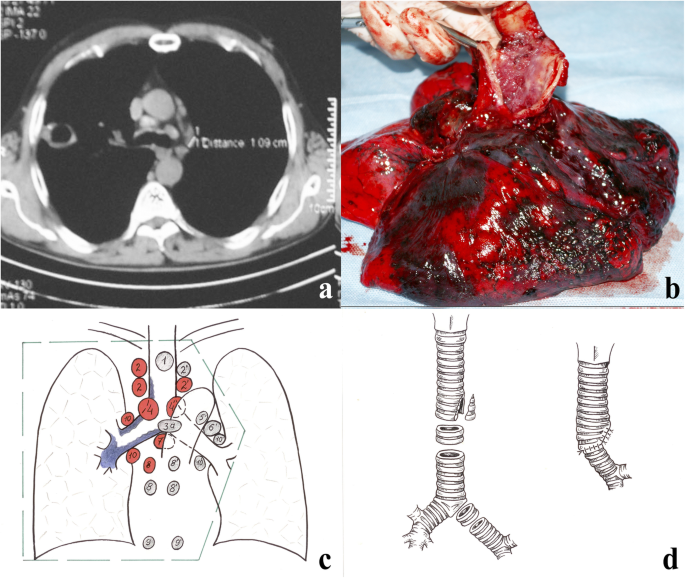

In 2007, cavitary tuberculosis of the right upper lobe was diagnosed (Fig. 1a). MTB resistant to isoniazid and rifampicin was found in sputum. Fibrobronchoscopy has revealed cancer of the right main bronchus with a transition to the lower third of the trachea and the close sections of the left main bronchus. Highly differentiated squamous cell carcinoma (SCC) was cytologically and histologically verified.

In 2008, the patient was referred to the CRIT. Based on the sputum cultural results and X-ray pictures, fibro-cavitary TB of the right lung was diagnosed (Fig. 1b). Central peribronchial highly-differentiated SCC of the right upper lobe with trachea invasion, T4N3M0 (IIIB), complicated by hemoptysis, was diagnosed based on histological and cytological studies and X-rays. Due to the specific diagnostic methods’ applications, there was no doubt about the diagnosis. Given the presence of TB and the possibility of life-threatening pulmonary hemorrhage in a patient who, otherwise, was in a relatively good condition, we determined that surgical treatment was practicable, despite lung cancer spread on the background of anti-TB therapy (ofloxacin, amikacinum, prothionamide, ethambutol, pyrazinamide).

An extended combined right pneumonectomy was performed with circular resection of the tracheal bifurcation and bilateral lymphadenectomy from transsternal access using combined endotracheal anesthesia (Fig. 2a-d). A bilateral mediastinal dissection was performed from the median sternotomy with the excision of 1, 2, 3a, 4–9 groups of lymph nodes (Fig. 1c). The right lung with a tracheal segment and one left main bronchus half-ring were removed together with the palpation borders. At this stage, a left main bronchus jet-ventilation was performed through the sternotomy.

After evaluating the possibility of further resection, two more tracheal and two left main bronchus half-rings were dissected. The final resection line of the trachea and bronchus was 0.5–1.0 cm from the tumor’s edge. An urgent histological examination of the resection line was not carried out because a larger volume of resection was considered impossible. The diastasis between the trachea and the left main bronchus after complete excision of the pathology was more than 5 cm. Wedge resection of the tracheal cartilage portion on the left border with a membranous part was followed by defect suturing. High-tension anastomosis formation on the jet ventilation tube was performed to narrow the tracheal diameter to that of the bronchial stump (Fig. 1d).

Histological, cytological, and microbiological studies of the surgical material confirmed TB and SCC of the trachea and right upper lobe bronchus combination. No tumor invasion was detected along the resection line of the trachea and bronchus.